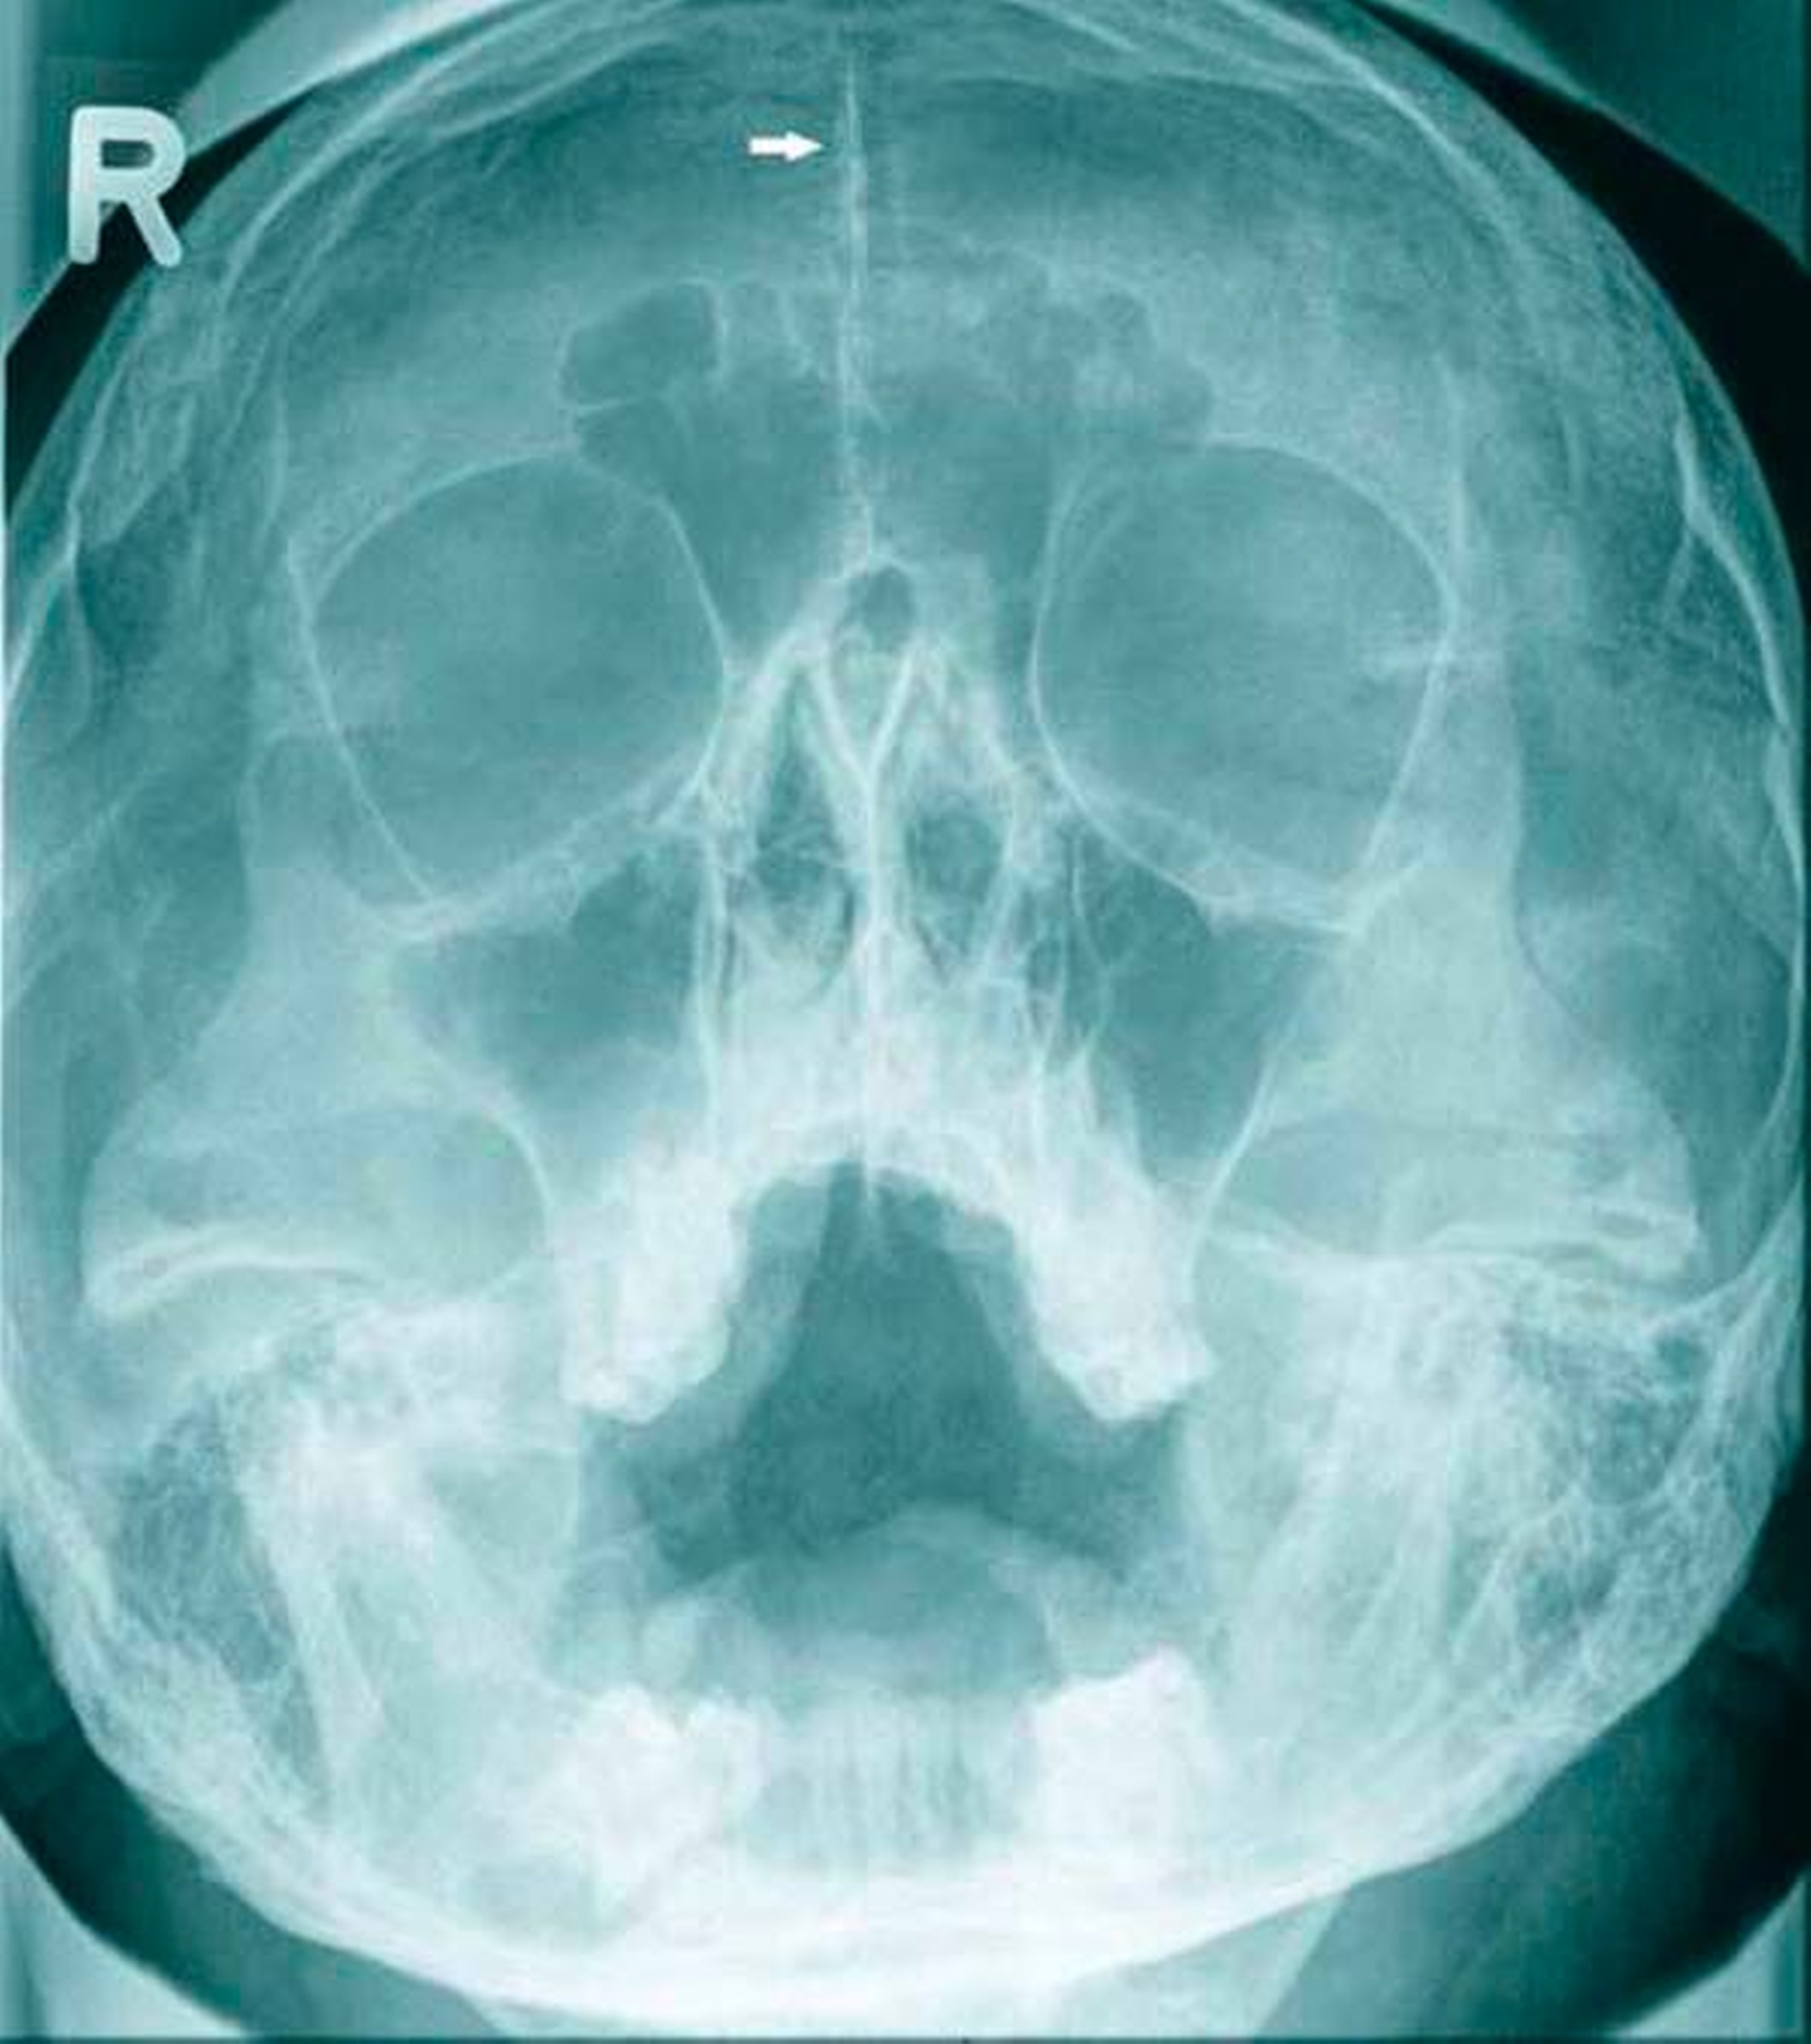

Ein 17-jähriger Patient wurde mit einer odontogenen Zyste im rechten Oberkiefer überwiesen (Abbildung 1). Bereits fünf Jahre zuvor waren bei ihm multiple Keratozysten entfernt und der Verdacht auf ein Gorlin-Goltz-Syndrom geäußert worden, dieser wurde jedoch nicht weiter abgeklärt. Anamnestisch lagen bisher keine Basalzellkarzinome vor.

Zur weiteren Beurteilung der Ausdehnung des Befunds wurde eine Nasennebenhöhlenaufnahme veranlasst (Abbildung 2). Darin zeigte sich eine deutlich sichtbare Verkalkung der Falx cerebri, was den klinischen Verdacht eines Gorlin-Goltz-Syndroms nach den Evans-Kriterien (Tabelle 1) [Evans et al.] bestätigte. Ein weiteres auffälliges Merkmal: ein vergrößerter Augenabstand (Hypertelorismus). Weitere, angeborene Fehlbildungen lagen nicht vor, die Familienanamnese war negativ.